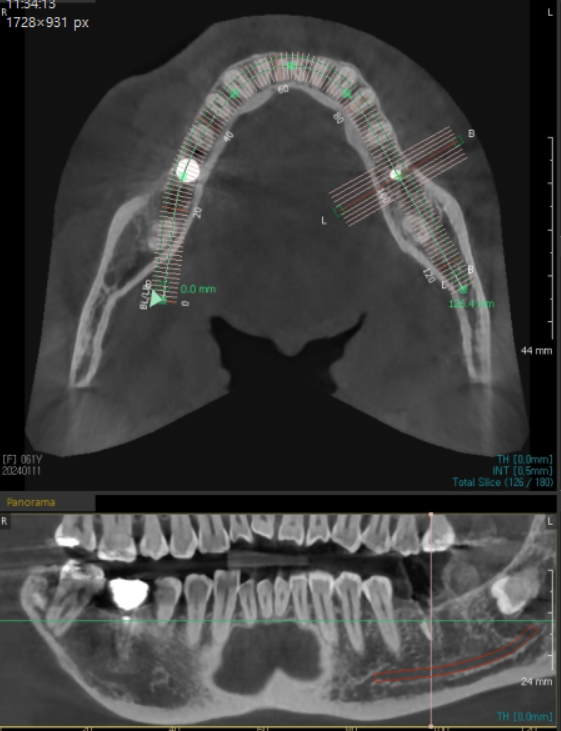

24.01.11

제가 놓치는 부분이 있을까

ct까지 찍어보았지만

뼈 이식 해야할 이유가 전혀 없었습니다.

아래 어금니 임플란트 ct로 뼈를 분석해서

충분한 부분에 심으면 뼈이식이 필요없거든요